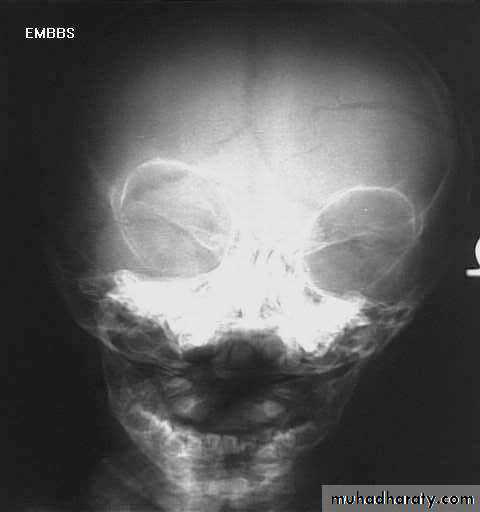

a. Plain skull x-ray

1. Can demonstrate the site and type of a skull fracture.

2. A foreign body can also be seen.

Skull Fracture

nurosurgery